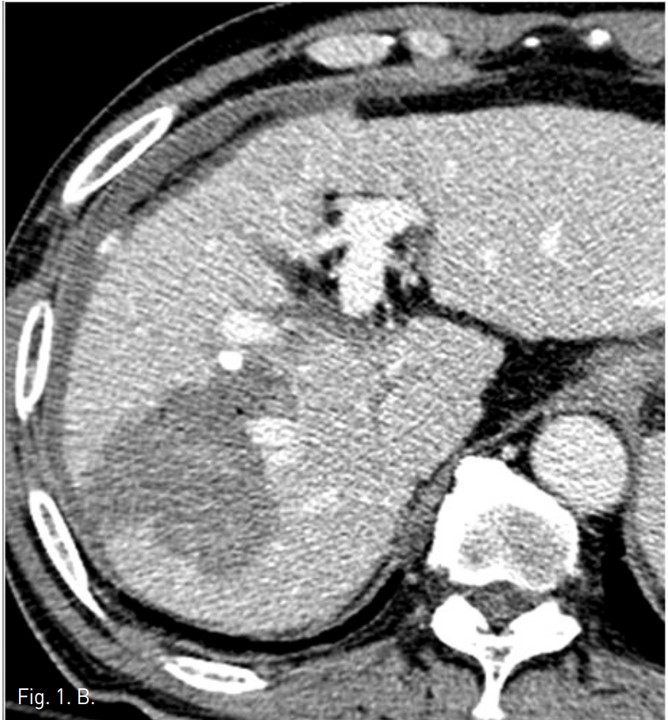

동맥기 간 CT 횡단면 영상에서 간우엽에 두 개의 간암의 크기가 증가되어 고주파 열치료를 시행하였다. 시술후 추적 CT에서 간우엽의 표면을 따라 조영제가 혈관 밖으로 흐르는 것이 발견되었고, 출혈성 복수의 양이 증가되었다 (Fig. 1).

Fig. 1. A

Fig. 1. Dynamic liver CT arterial (A) and portal (B) phase scans show extravasation (arrows) of contrast materials at the surface of the liver and hemoperitoneum around the liver. The focus of extravasation was not clear.